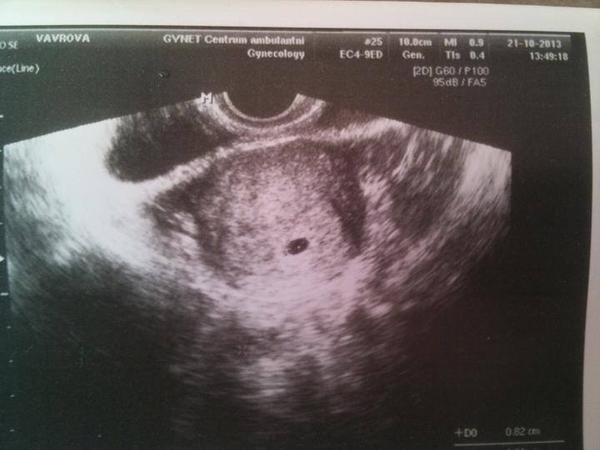

@maminka2020 muj utz 5+3 nevidela jsem skoro nic 😅

@maminka2020 mam stejnou fotku, bublinku jsem sice mela, ale malo viditelnou, skoro zadnou, taky jsem byla 6+1, srdicko jsem videla az za tyden a pul.